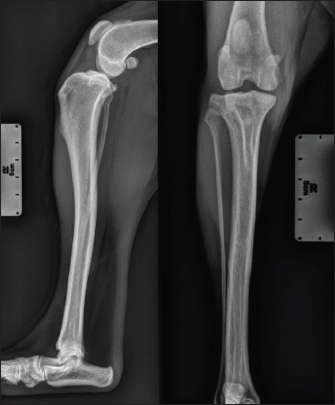

A 2-year-old female mixed-breed Shepherd weighing 15 kg, who suffered a trauma during play 3 months before, was presented with severe chronic lameness of the right hindlimb nonresponsive to NSAIDs. The orthopedic examination revealed a positive drawer test. The stress radiographs confirmed the suspicion of CdCL rupture with a displacement of the tibia relative to the femur (Fig. 1). A Liverpool osteoarthritis in dogs (LOAD) questionnaire was completed with the owner of the animal during the preoperative consultation, with a score of 22/52 indicating severe mobility impairment (Walton et al., 2013). A replacement of the CdCL by a synthetic UHMWPE ligament was decided using an arthroscopic approach.

Fig. 1. Radiographic views of the dog's right pelvic limb from side (left) and front (right) at the time of diagnosis.